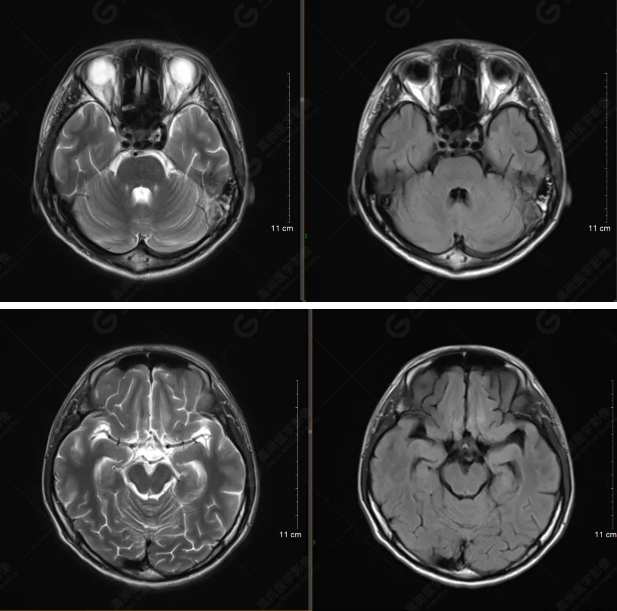

以下是T1WI軸位掃描及矢狀位掃描:

雙側(cè)大腦半球?qū)ΨQ,灰白質(zhì)對比正常,顱內(nèi)未見異常信號影。腦室系統(tǒng)未見擴(kuò)大,中線結(jié)構(gòu)居中。腦溝、裂未見增寬。幕下小腦、腦干未見異常。矢狀位示垂體形態(tài)、大小級信號未見異常。所示左側(cè)乳突內(nèi)見多發(fā)短T1長T2信號影。

顱腦MRI平掃未見明顯異常,左側(cè)乳突內(nèi)積血,建議補(bǔ)充SWI檢查。